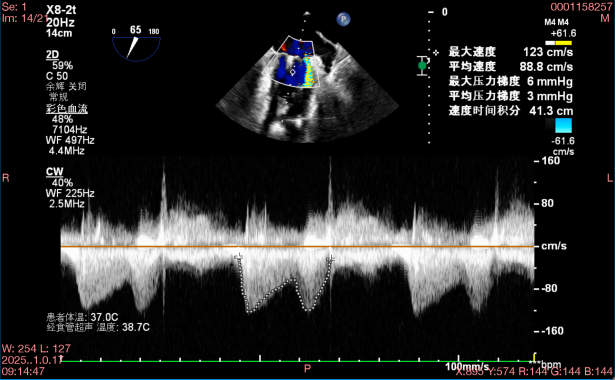

在全麻下,于心尖入路完成ValveClamp®装置植入。术中多学科团队密切配合,超声全程实时指导操作。最终,于2偏3区成功植入一枚Ⅲf夹子,一次夹合完成。前叶夹合量12mm,后叶夹合量10mm,反流降至1+,导管操作时间30分钟。术后平均跨瓣压差3mmHg。